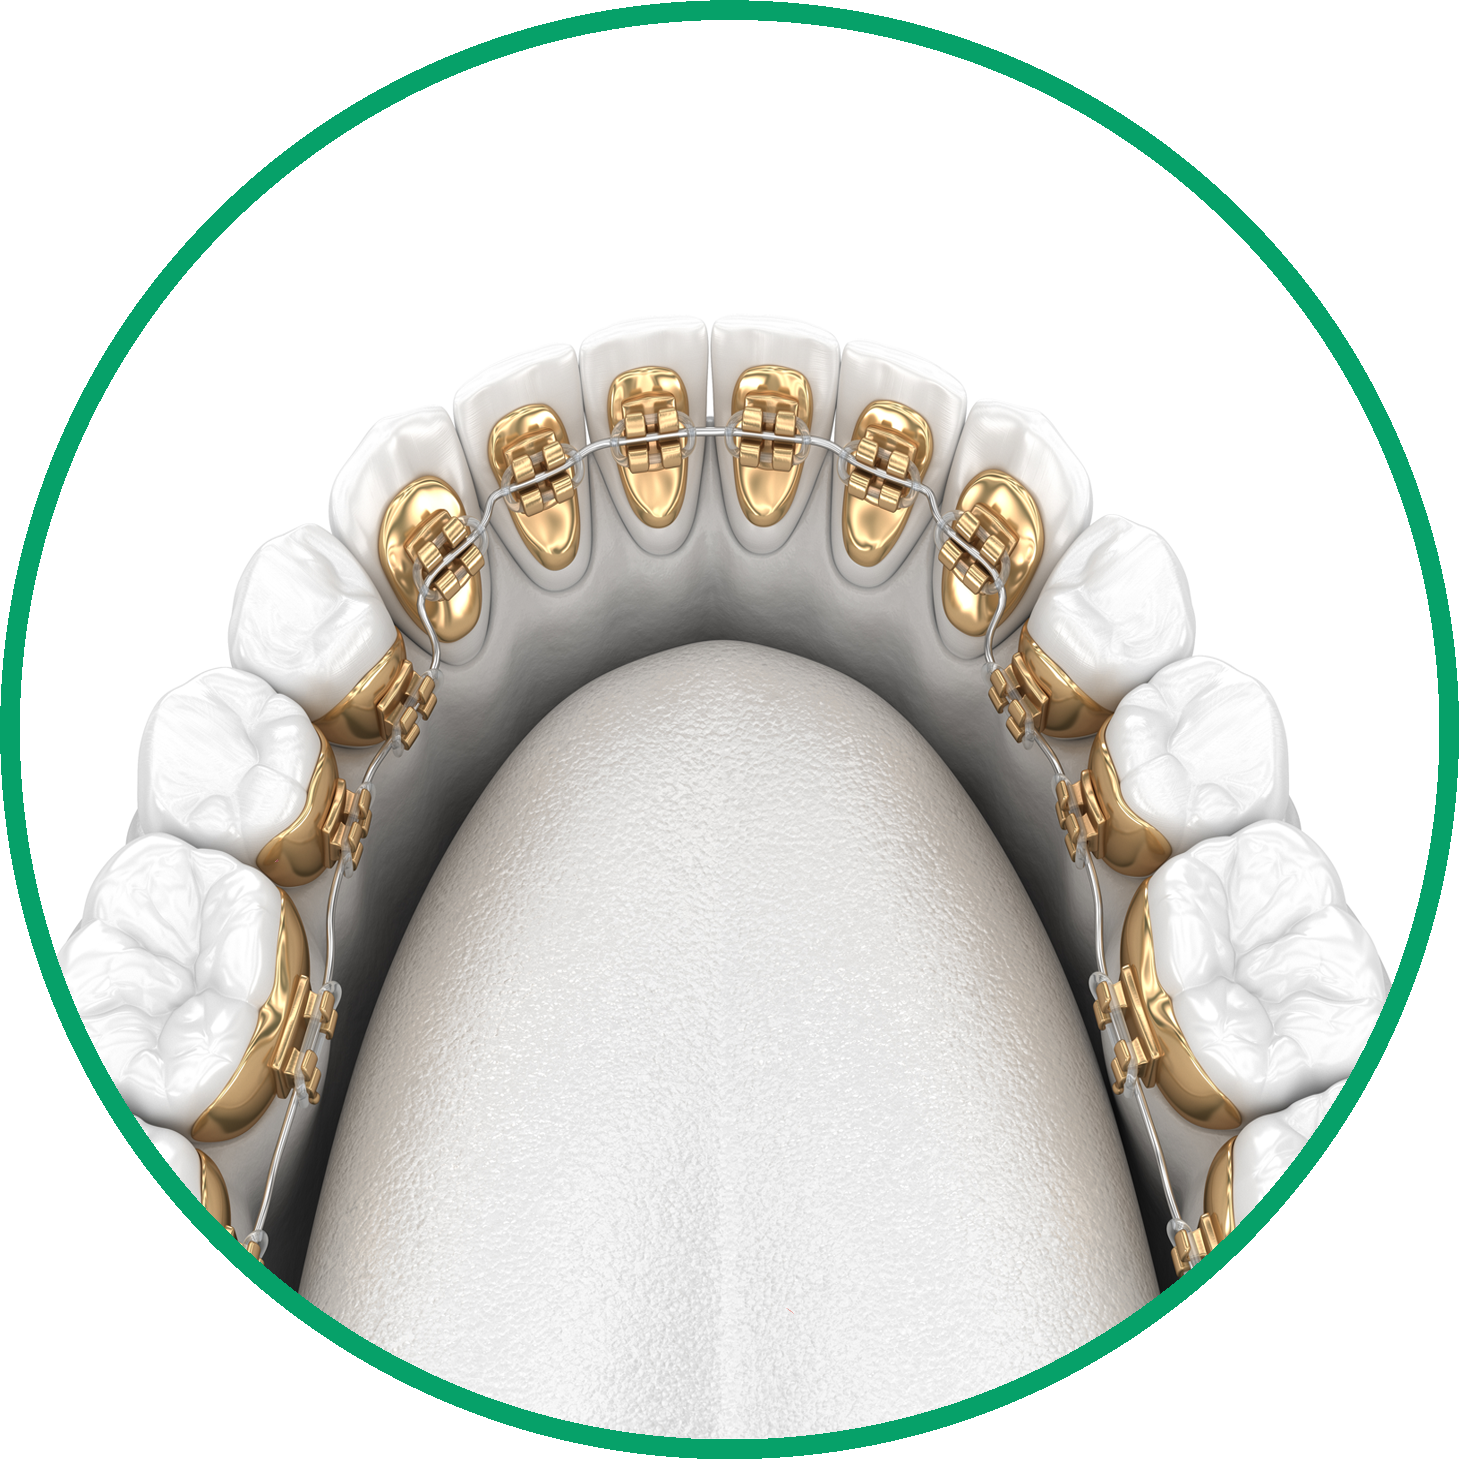

Además de los aparatos metálicos tradicionales, ofrecemos una variedad de opciones de ortodoncia, incluyendo alineadores transparentes, aparatos linguales y aparatos de cerámica, para dar cabida a las diversas necesidades y preferencias de nuestros pacientes.

Los aparatos más comunes son los brackets metálicos o cerámicos, los alineadores transparentes, los aparatos para la cabeza, los retenedores, los aparatos de expansión y los aparatos funcionales. El tipo utilizado depende de cada caso.